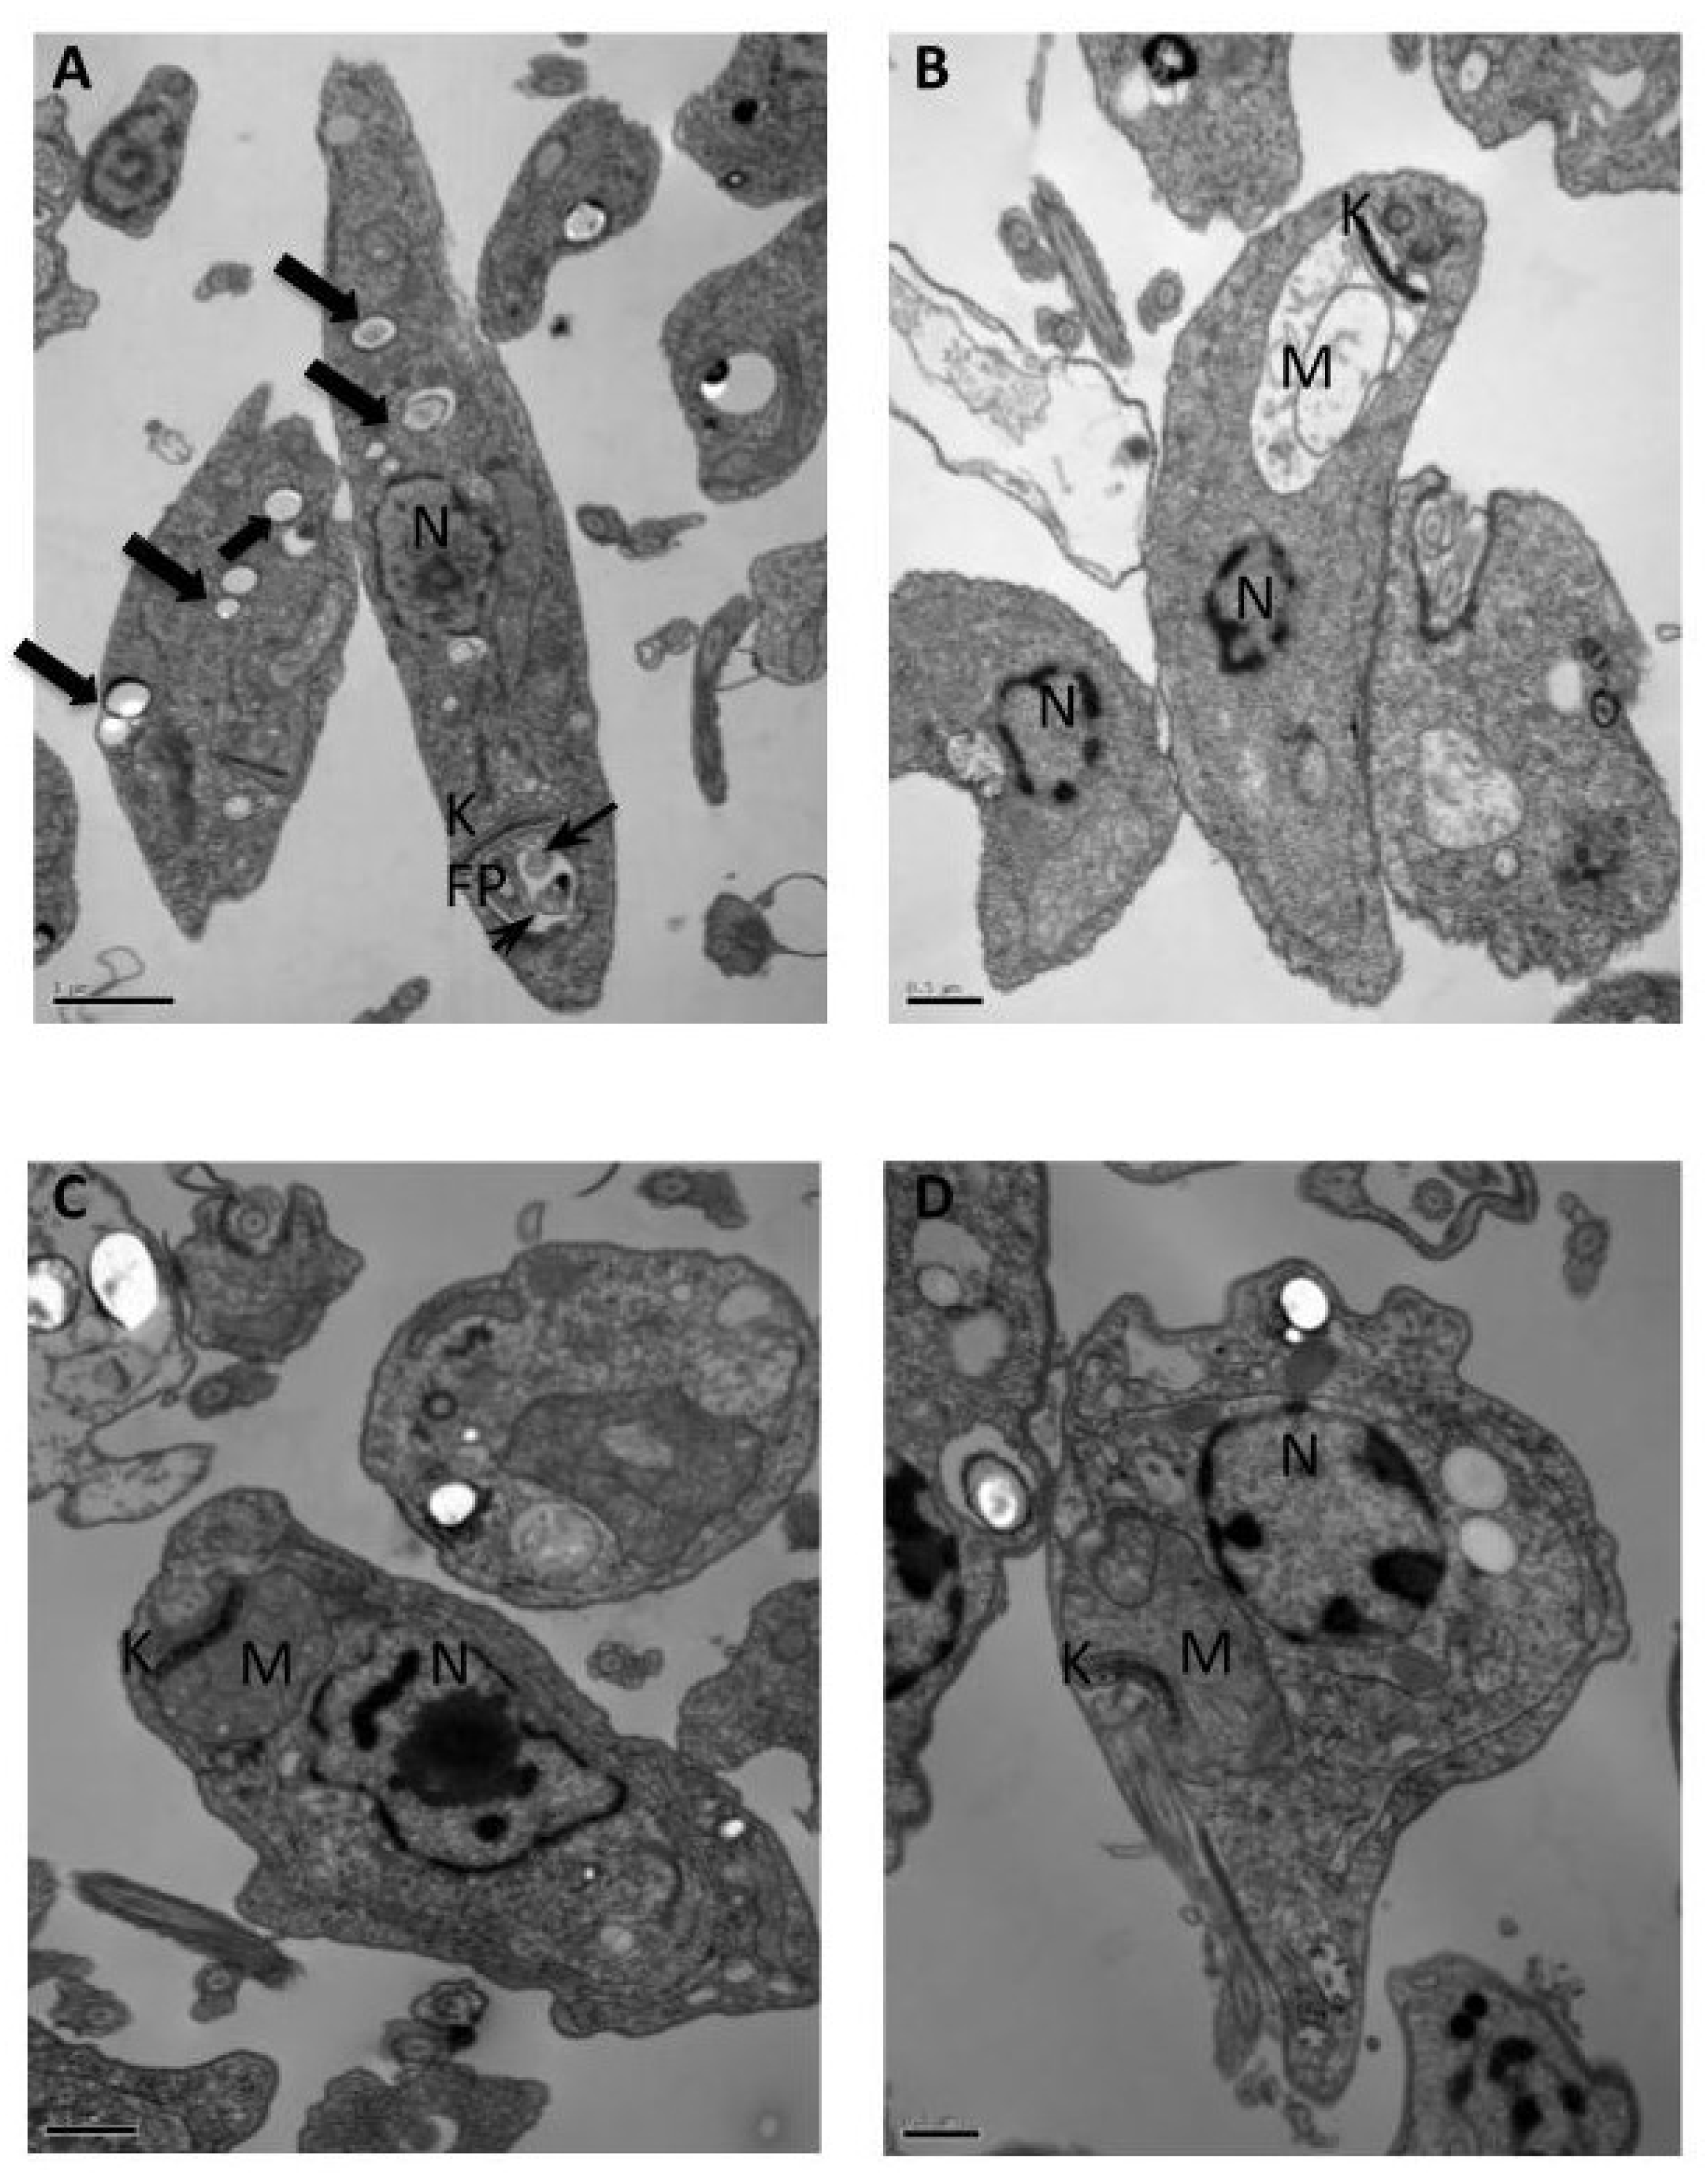

2.1. Transmission Electron Microscopy (TEM)

3.3.1. Transmission Electron Microscopy